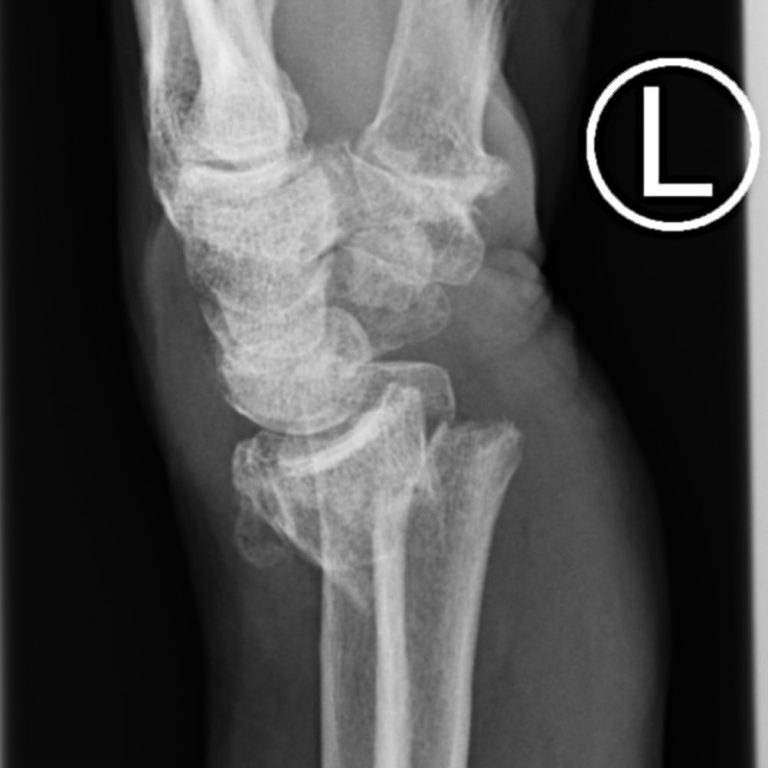

Unfälle

Unser Team ist spezialisiert auf die Diagnose und Behandlung von Sportverletzungen, Arbeits- und Schulunfällen, Schnitt- und Platzwunden, Knochen- und Wirbelbrüche sowie die Nachsorge nach Operationen.